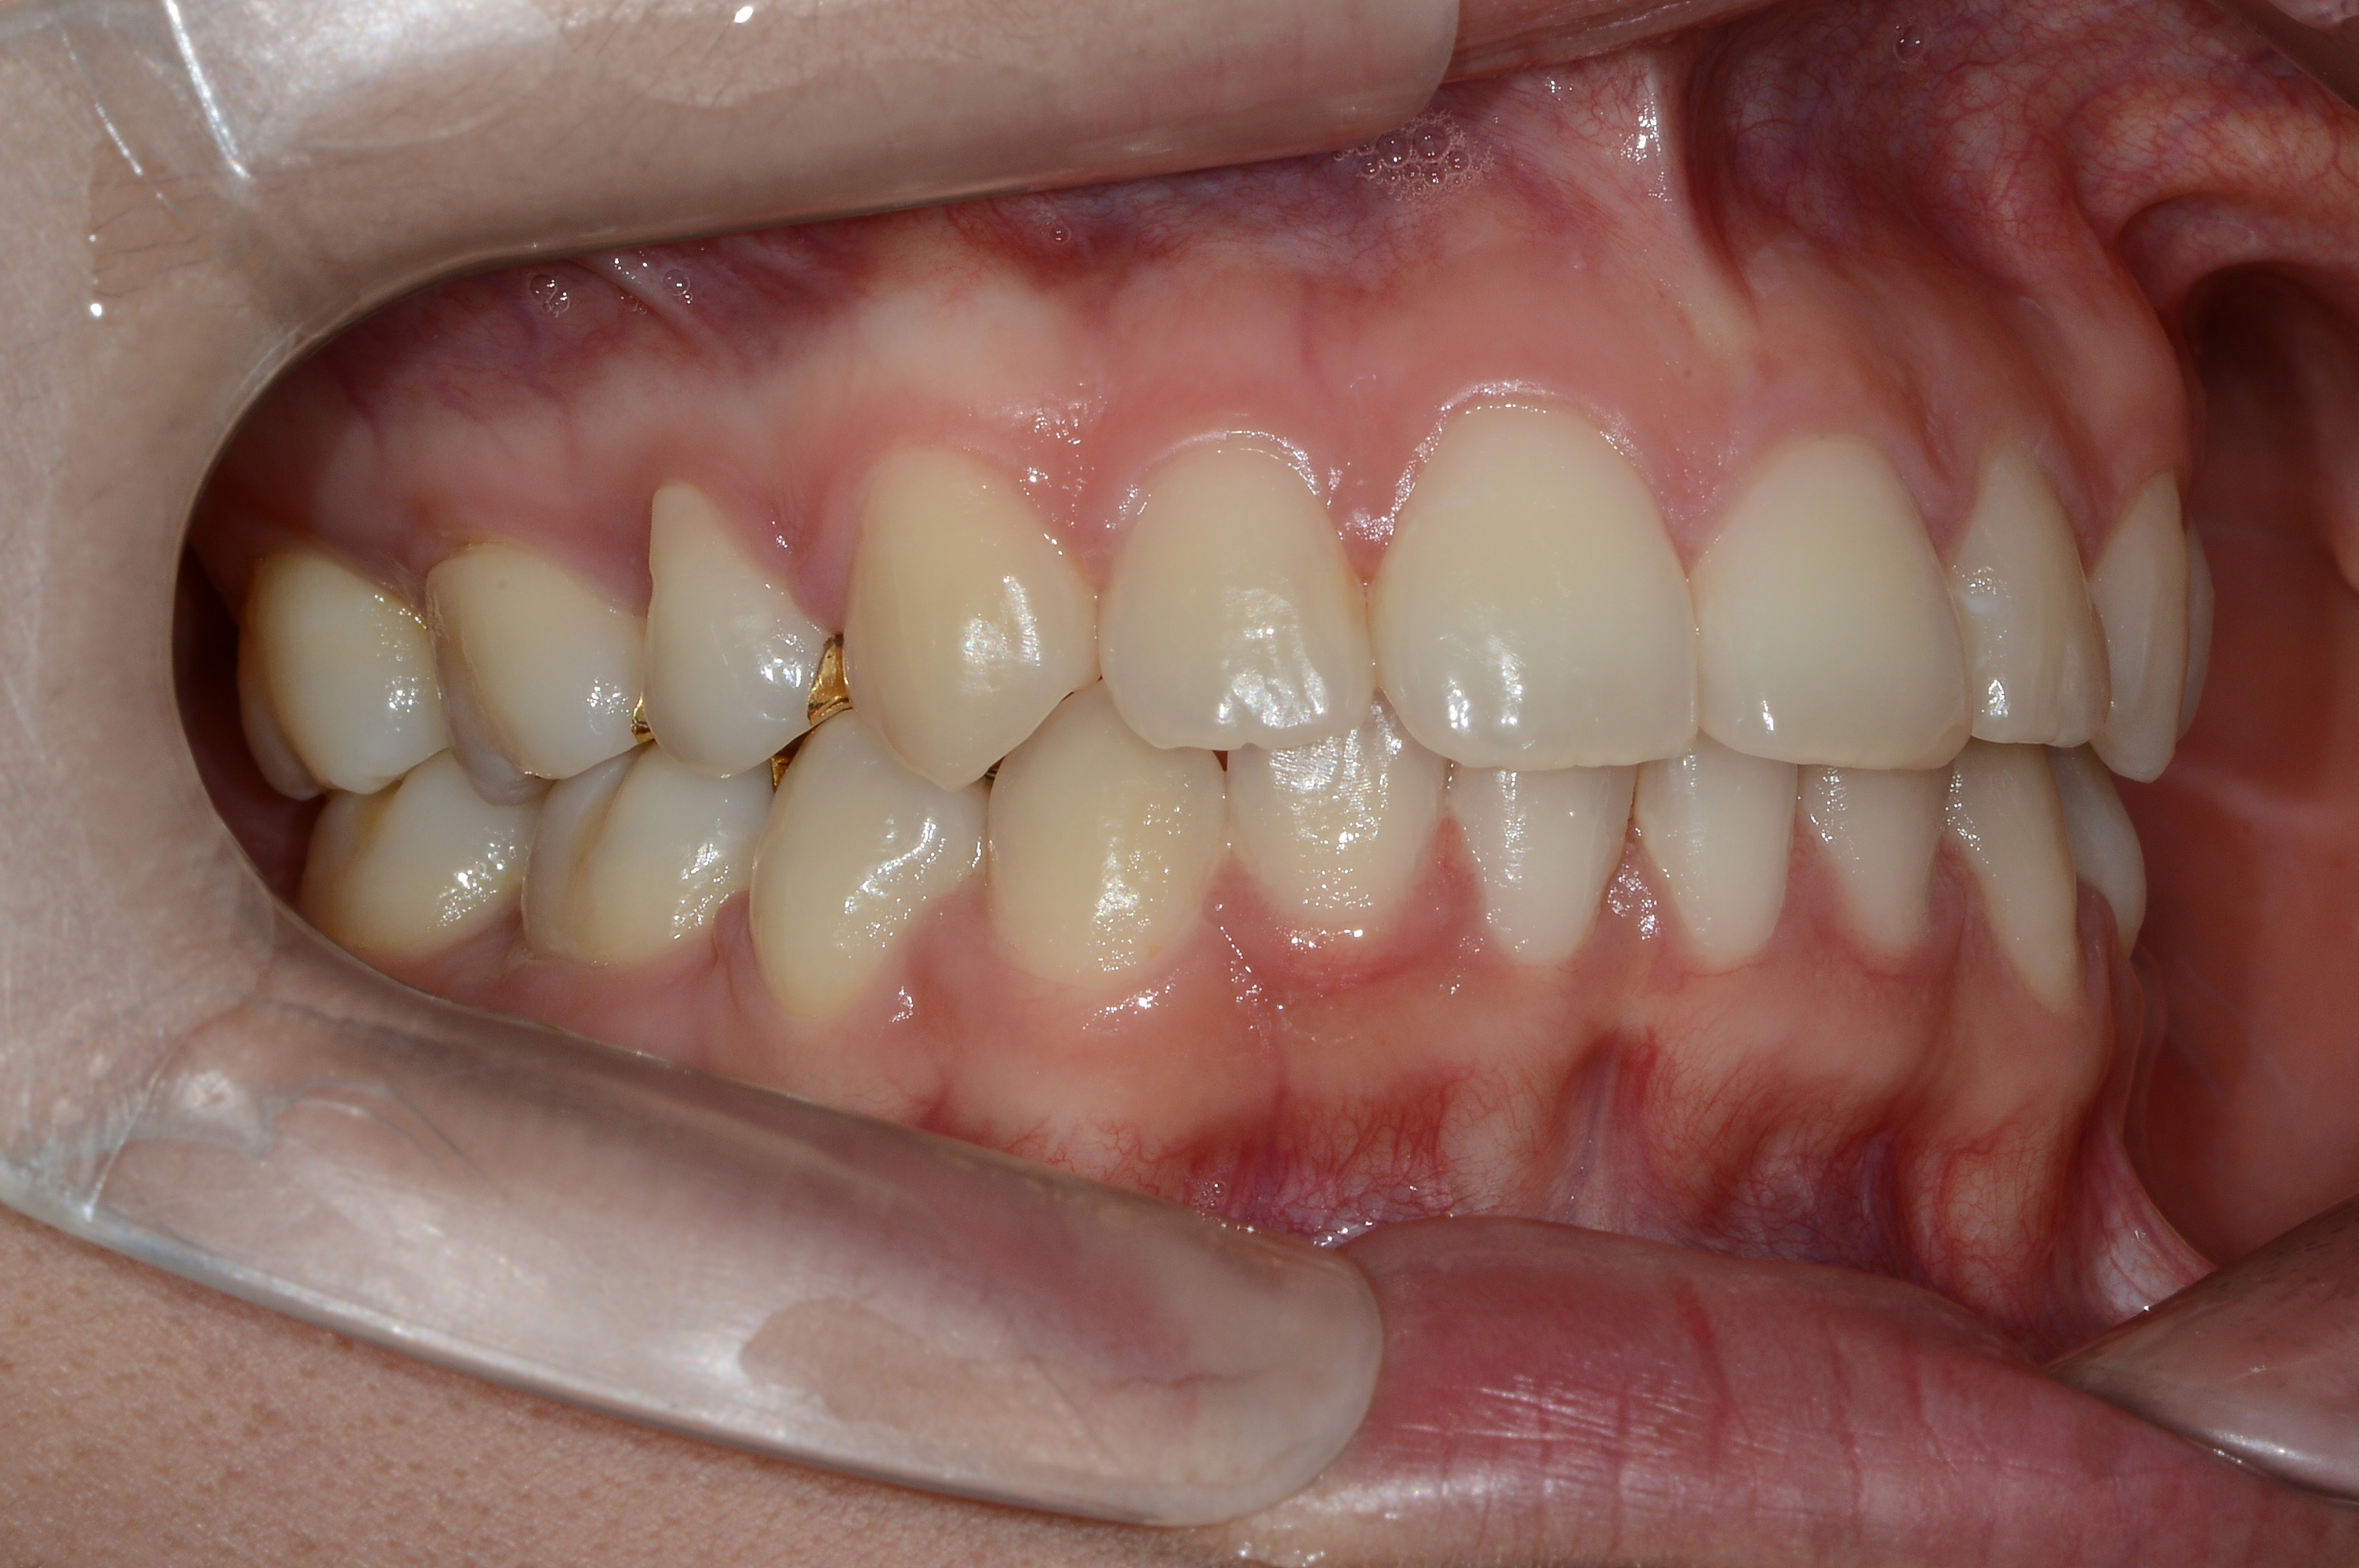

치료 후 사진입니다.